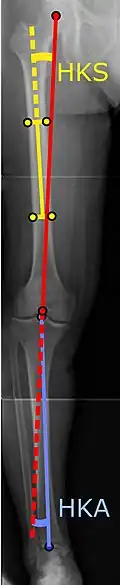

To indicate knee replacement in case of osteoarthritis, its radiographic classification and severity of symptoms both should be substantial. Such radiography should consist of weightbearing X-rays of both knees: AP, lateral, and 30 degrees of flexion. AP and lateral views may not show joint space narrowing, but the 30-degree flexion view is most sensitive for narrowing. Full-length projections also are used in order to adjust the prosthesis to provide a neutral angle for the distal lower extremity. Two angles used for this purpose are:

- Hip-knee-shaft angle (HKS),[10] an angle formed between a line through the longitudinal axis of the femoral shaft and its mechanical axis, which is a line from the center of the femoral head to the intercondylar notch of the distal femur.[12]

- Hip-knee-ankle angle (HKA),[11] which is an angle between the femoral mechanical axis and the center of the ankle joint.[12] It is normally between 1.0° and 1.5° of varus in adults.[13]

![HKA: Hip-knee-ankle angle, which is ideally between 3° varum to 3° valgum from a right angle.[62]](./X-ray_of_HKA_angle_with_knee_prosthesis.jpg)